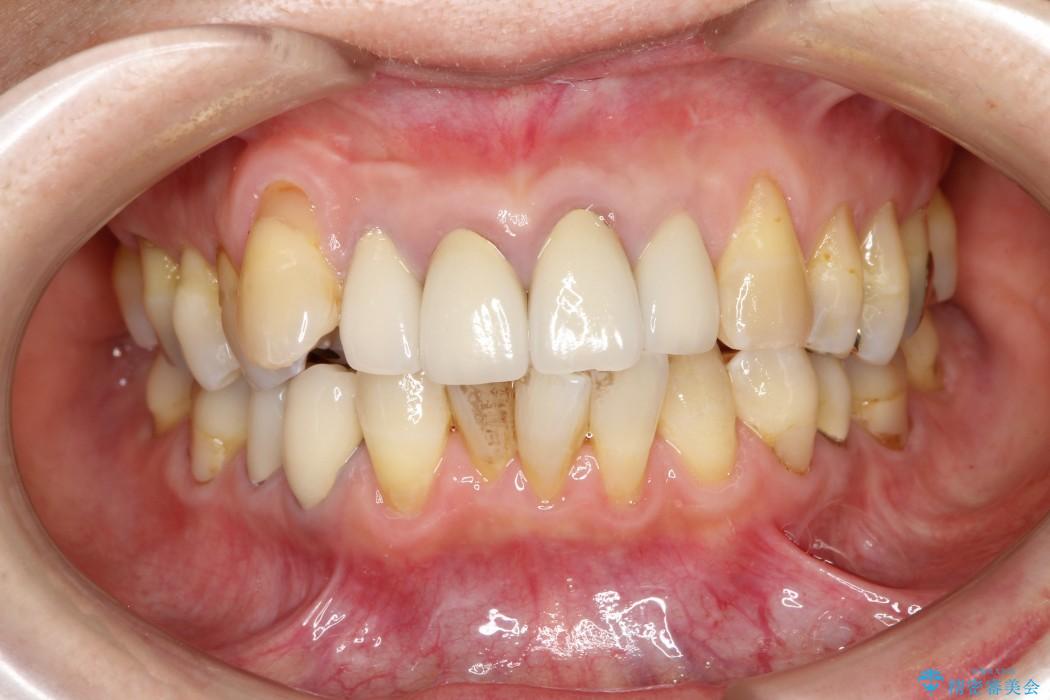

【50代女性】八重歯のインビザライン矯正 治療例

八重歯の改善を希望され来院されました。

当初はセラミックでの治療を希望されていましたが、噛み合わせと歯並びを治していく為に矯正治療を提案させていただき、インビザラインでの矯正を行う計画にしました。